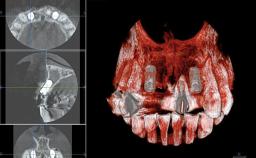

In 2001, a 48-year-old woman presented at a dental clinic with a failing fixed partial denture spanning from teeth 13 to 21. She was experiencing pain upon function, tenderness to palpation facial to tooth 13, and severe mobility of the prosthesis. Radiographic and clinical assessment revealed a subcrestal fracture of tooth 13, making its restoration unlikely. It was determined by the clinician that the tooth needed to be extracted prior to proceeding any further with dental care. After the extraction, the patient lost confidence in the progression of her treatment and sought consultation at the Center for Implant Dentistry. At her consultation visit in our clinic, an extra- and intraoral clinical examination revealed a medium lip line at full smile and an edentulous area spanning from 13 to 12 with both vertical and horizontal deficits in hard and soft tissue.

Bone Augmentation Horizontal|Staged|Vertical

Augmentation Materials Autogenous chips|Autogenous block(s)|Membrane

Bone Volume Deficient vertically or deficient vertically AND horizontally